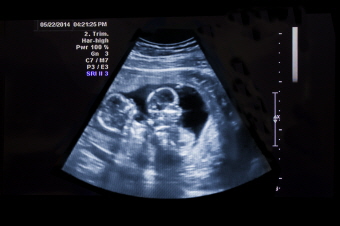

초음파 검사에서 두 명 이상의 태아가 확인될 뿐만 아니라 두 개 이상의 심음이 들립니다.

겉모습으로 볼 때 임신 주수에 비해 산모의 배가 클 경우 다태아를 의심합니다. 초음파상으로 태아가 한 명 이상인 것을 확인하면 다태아를 확진합니다.